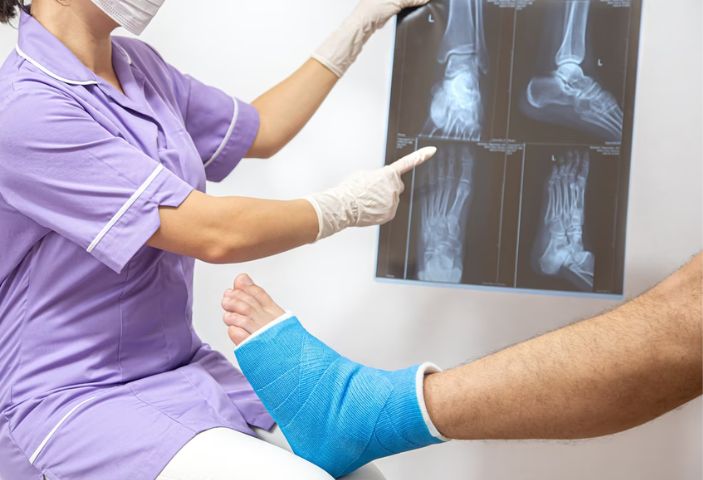

Gãy xương được chẩn đoán thông qua các triệu chứng kết hợp kết hợp với thực hiện các xét nghiệm, chẩn đoán hình ảnh.

- Thăm khám lâm sàng: phát hiện triệu chứng điển hình của gãy xương, phân loại gãy xương và đưa ra các chỉ định chẩn đoán hình ảnh tương ứng.

- Thực hiện kỹ thuật chẩn đoán hình ảnh (Xquang, CT, MRI): Phương pháp này tạo ra những hình ảnh hai chiều về xương, giúp bác sĩ xác định rõ các vết gãy, mức độ tổn thương xương, khớp, các cơ quan, phần mềm, mô, gân, cơ, dây chằng… lân cận và đưa ra phương pháp điều trị phù hợp.